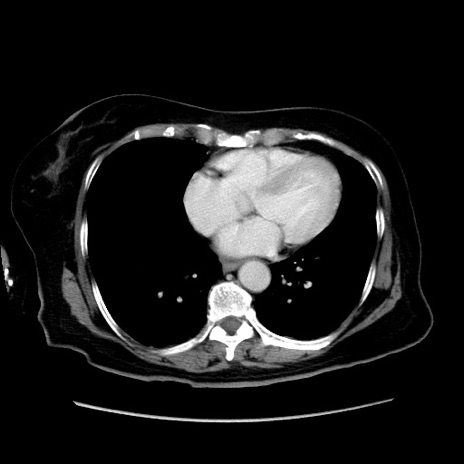

症例19(横断像)

【症例】80歳代女性

【主訴】下腹部痛

【現病歴】約8時間前より下腹部痛の出現あり、救急外来受診。

【既往歴】両側付属器切除

【身体所見】意識清明、下腹部正中に手術痕あり、その部位に一致して圧痛と反跳痛あり。腸蠕動音は亢進。

【データ】WBC 9300、CRP 0.15